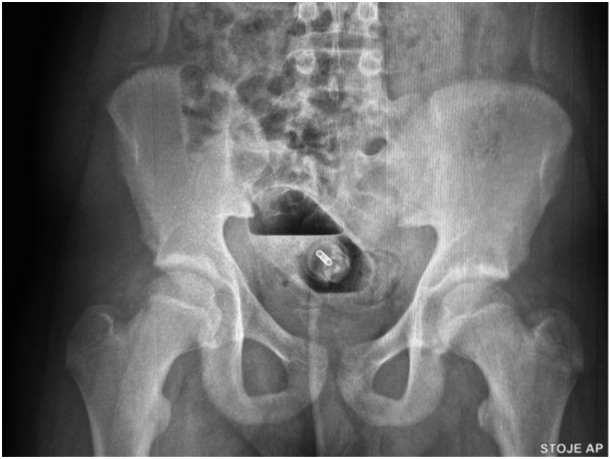

Foreign bodies (FBs) in the lower gastrointestinal tract are sporadically described in children. The therapeutic approach is individualized, depending on the type of FB, the location, time since insertion and the severity of bowel injuries. These FBs can be frequently removed manually or endoscopically. However, exploratory laparotomy is inevitable in unsuccessful and complicated cases. Herein we present a teenager boy with a self-inserted large perfume bottle in the sigma, and we performed the review of the published literature.